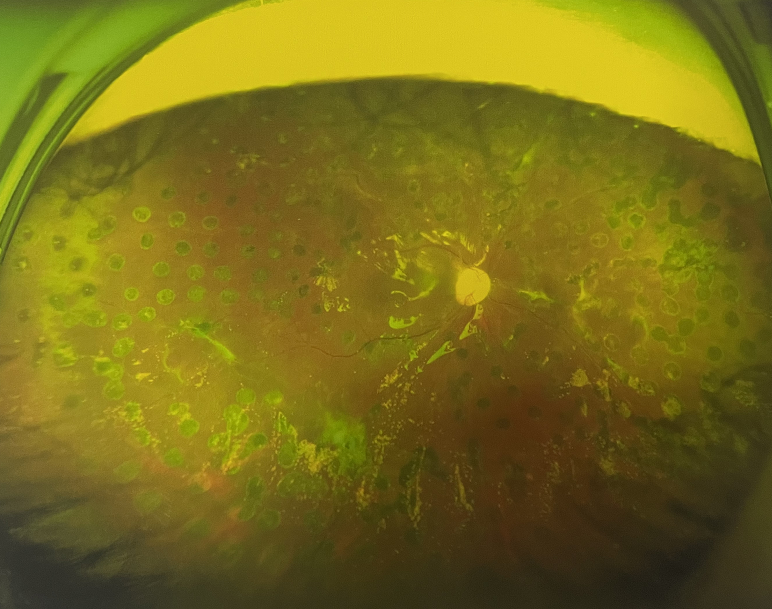

張小虎醫(yī)生為王女士進(jìn)行右眼玻璃體腔注藥術(shù),3天后進(jìn)行右眼23G玻璃體切割術(shù)后視力有所提升。

4個(gè)月后王女士來(lái)院取硅油,取油后視力恢復(fù)到0.6。“當(dāng)時(shí)來(lái)的時(shí)候真的只能看到模糊的影子,特別害怕覺(jué)得完了,想說(shuō)眼睛估計(jì)要瞎了,沒(méi)想到手術(shù)后視力竟然提升了,現(xiàn)在也看得比較清楚了。”王女士說(shuō)到。

張小虎醫(yī)生表示,糖網(wǎng)病進(jìn)展到嚴(yán)重增殖期帶來(lái)的視力損傷往往是極其嚴(yán)重的,目前王女士右眼從術(shù)前0.02恢復(fù)到術(shù)后0.6,已屬十分難得。

右眼術(shù)后